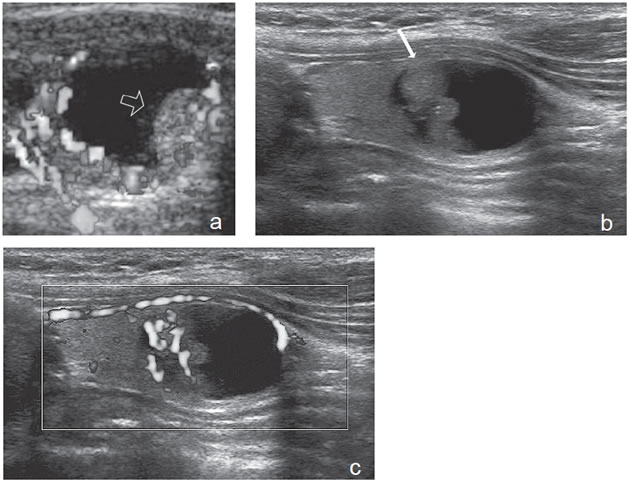

Un nódulo coloideo mixto puede aparecer como un quiste con un nódulo mural isoecogénico, excéntrico, que protruye hacia el lumen simulando una formación papilar, habitualmente vascularizado, que no corresponde a tejido neoplásico (Figura 19a). Si el componente sólido está rodeado por fluido, separado de la pared, y además tiene focos hiperecogénicos, es más difícil confundirlo con un tumor quístico (Figura 19b y c).

Figura 19. a) Nódulo coloideo, que muestra

una proyección de aspecto papilar hacia

el lumen, que corresponde a tejido no

neoplásico, igualmente vascularizado que

el resto del componente sólido del nódulo

(flecha abierta); b) y c) Nódulo coloideo,

predominantemente quístico, con componente

sólido (flecha), que muestra una forma

vegetante completamente rodeada de

coloide, con dos focos puntiformes en el

área más central.